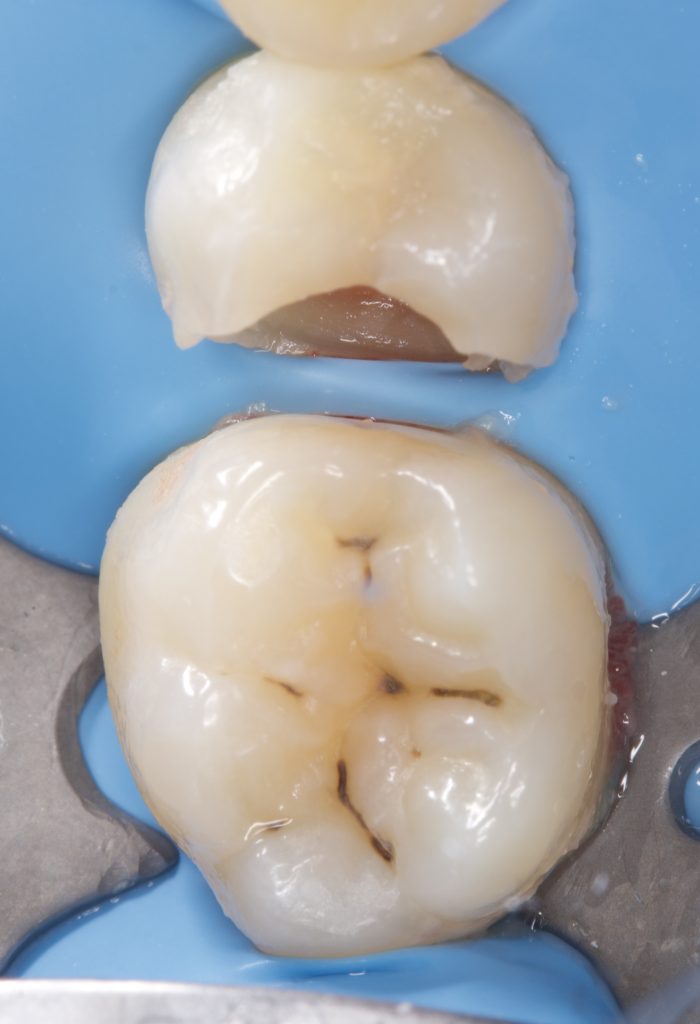

Step 4 – Fiber-Reinforced Base Layer

- A fiber-reinforced composite (EverX) was placed as a dentin replacement, covering pulpal and axial walls to enhance fracture resistance.

Step 5 – Flowable Composite Adaptation

- A Nano Flowable Composite (3M) was applied as a thin liner over the fiber-reinforced layer for intimate adaptation to irregularities.

- In deep areas, a Bulk Flow Composite (Shofu) was used to fill the base, reducing polymerization stress.

Step 6 – Functional Matrix Technique (FMT)

- The occlusal anatomy was pre-modeled on the matrix side before final curing, ensuring precise cusp-fossa reproduction and minimal occlusal adjustment.